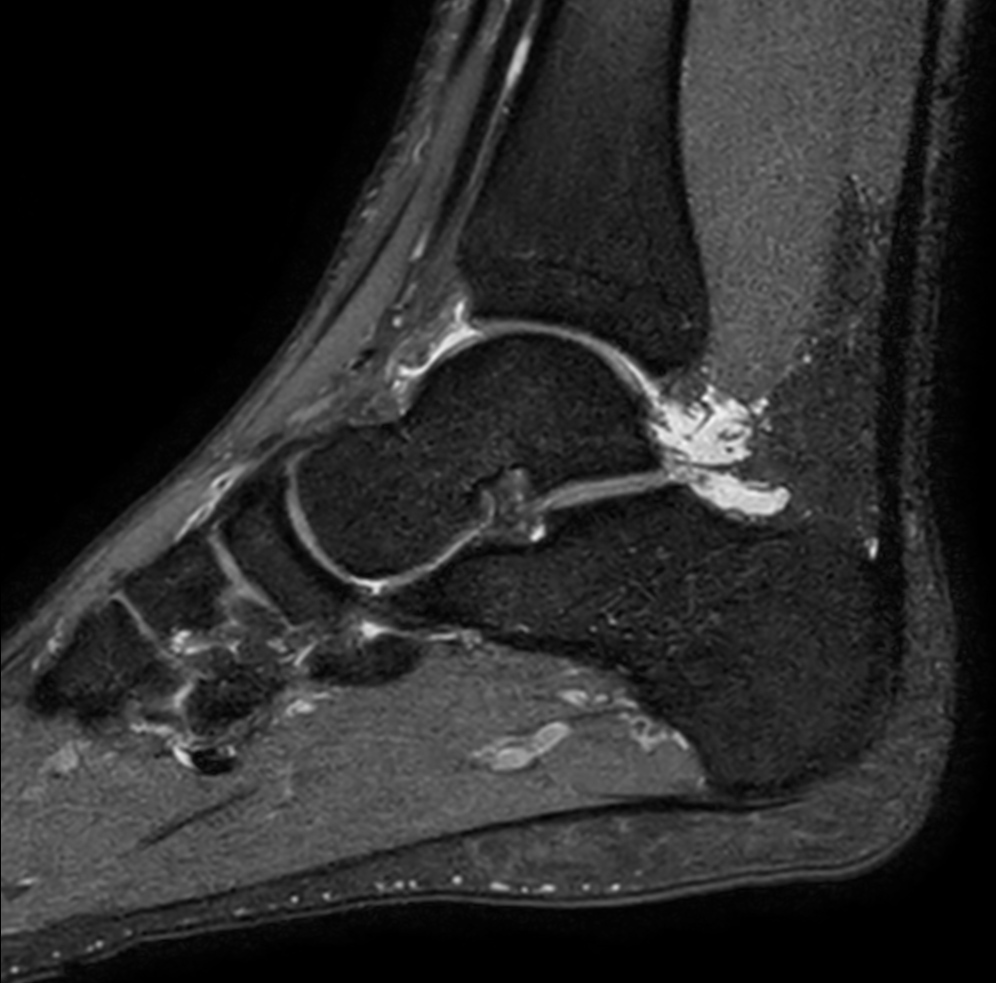

High resolution Ankle imaging in short scan times

Spital Uster, Switzerland

Sagittal T1w TSE - mDIXON XD (In Phase)Post-gado

Sagittal T1w TSE - mDIXON XD (Water only)Post-gado